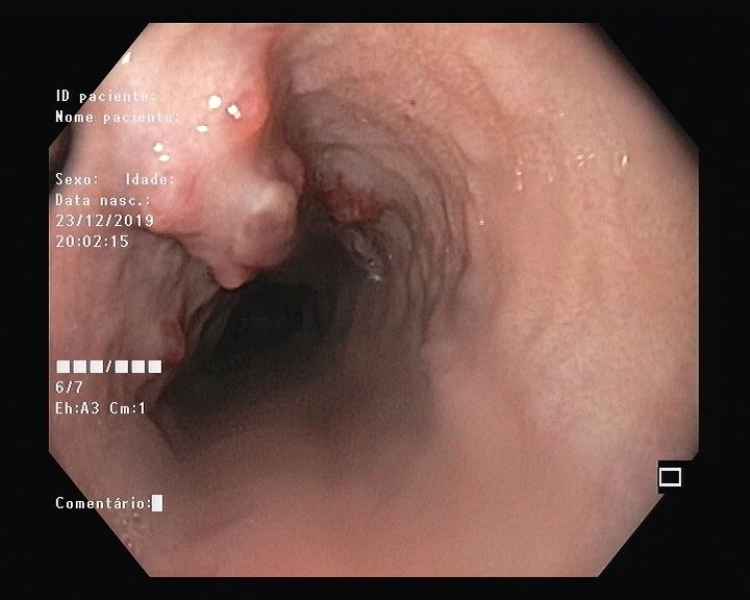

Unusual esophageal polyps in the context of advanced cirrhosis

Fotografias